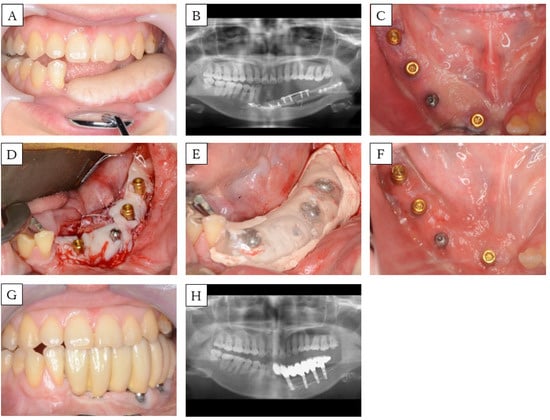

3.2. Case 3 (Method 2)

| Case | Age (years) | Sex | Cause | Mandible Defect Size (cm) | Mucosal Defect Size (cm) | No. of Implants | View | FGG | Fixing Method of Mucosal Graft | Prosthesis | Timing * (months) | Implant Lost |

|---|---|---|---|---|---|---|---|---|---|---|---|---|

| 1 | 46 | M | SCC | 6.5 | 3 × 2 | 2 | ![]() | no | - | Fixed | - | 1 |

| 2 | 58 | F | SCC | 5 | 4.5 × 1.5 | 3 | ![]() | yes ** | Method 1 | Fixed | 0 | 0 |

| 3 | 30 | F | OS | 7 | 5 × 1 | 4 | ![]() | yes | Method 2 | Fixed | 3 | 0 |

| 4 | 63 | M | SCC | 5 | 5 × 4 | 4 | ![]() | yes | (1) Method 2 *** (2) Method 3 | Removable | (1) 7 (2) 31 | 0 |

| 5 | 66 | M | ORN | 17 | All Gingiva | 4 | ![]() | yes | Method 3 | Removable | 0 | 0 |